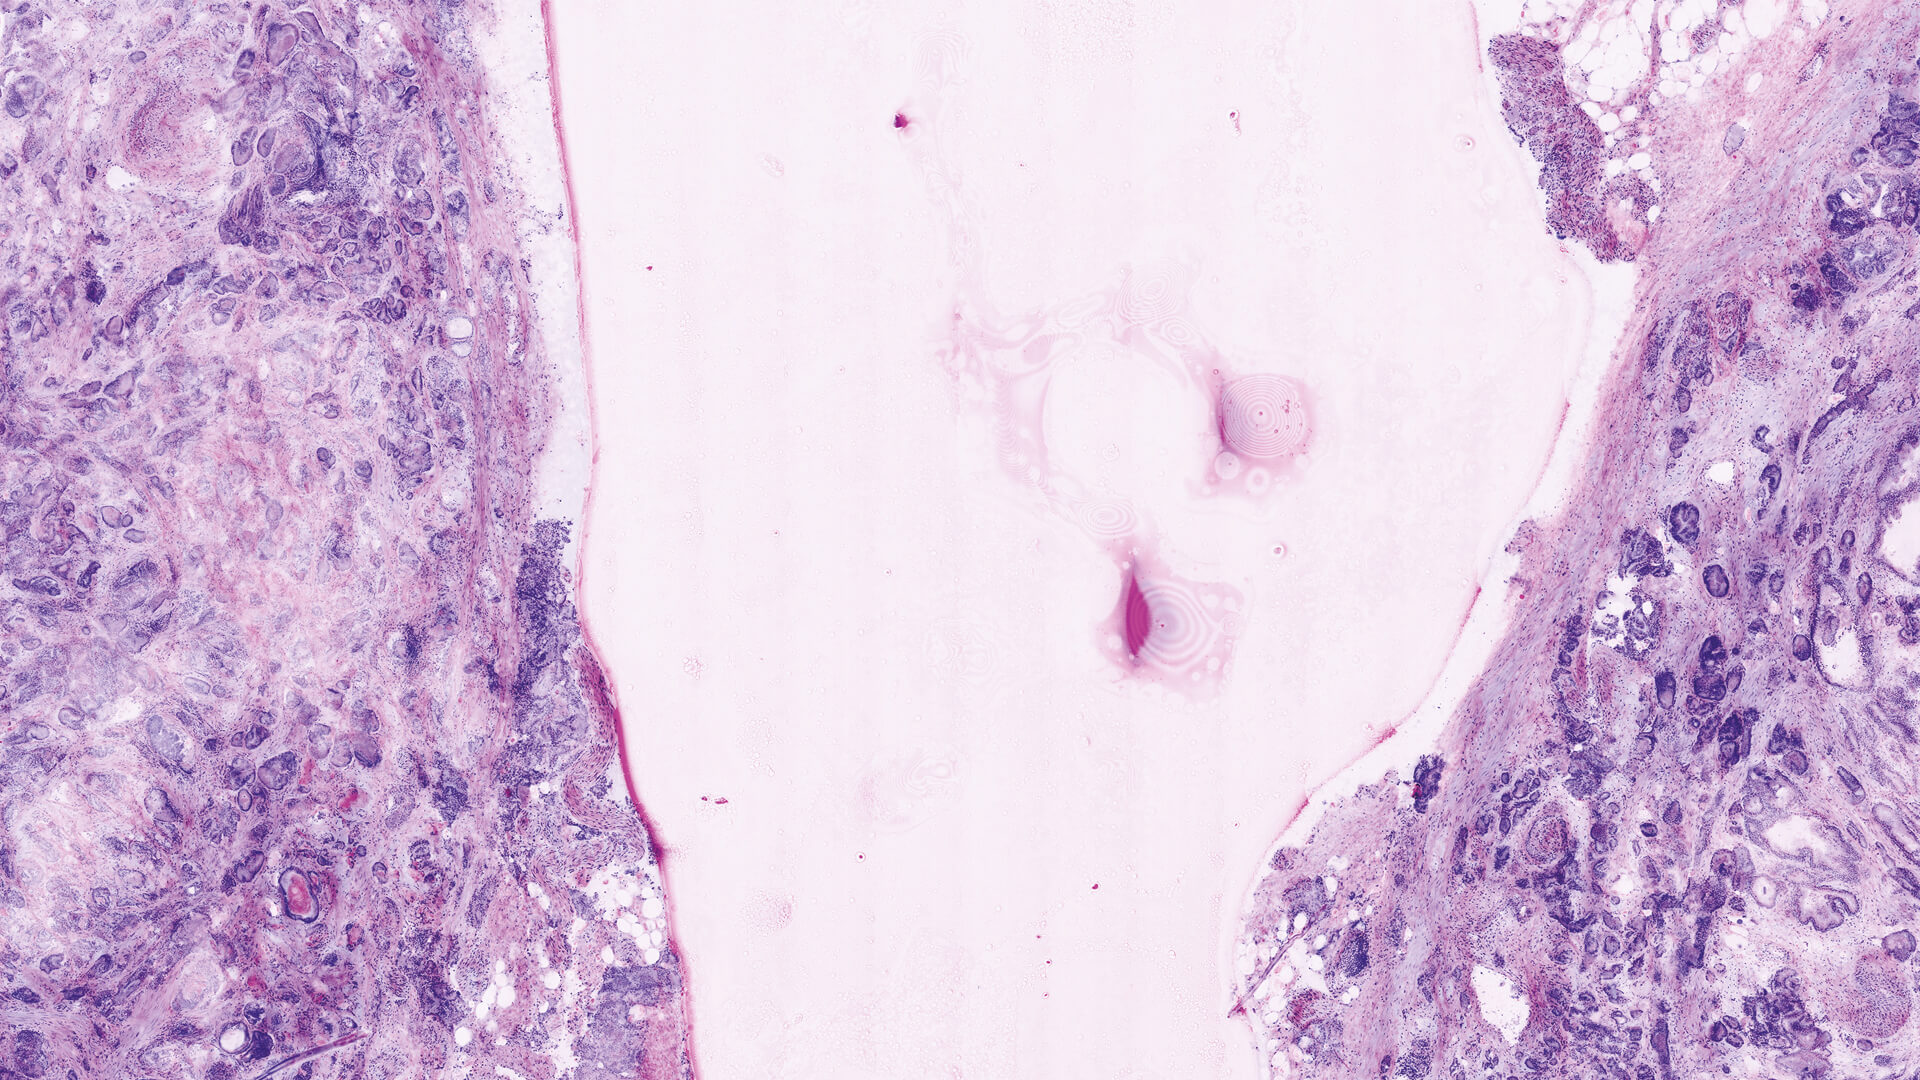

Two lasers of different wavelengths create two distinct images, a fluorescence image and a reflectance image. Both signals are scanned simultaneously and are used to create pseudo-colored images. The device’s software uses an algorithm to translate the acquired image information into colors that resemble H&E.

Basal cell carcinoma; imaged with the VivaScope 2500 (left) and after H&E staining (right)